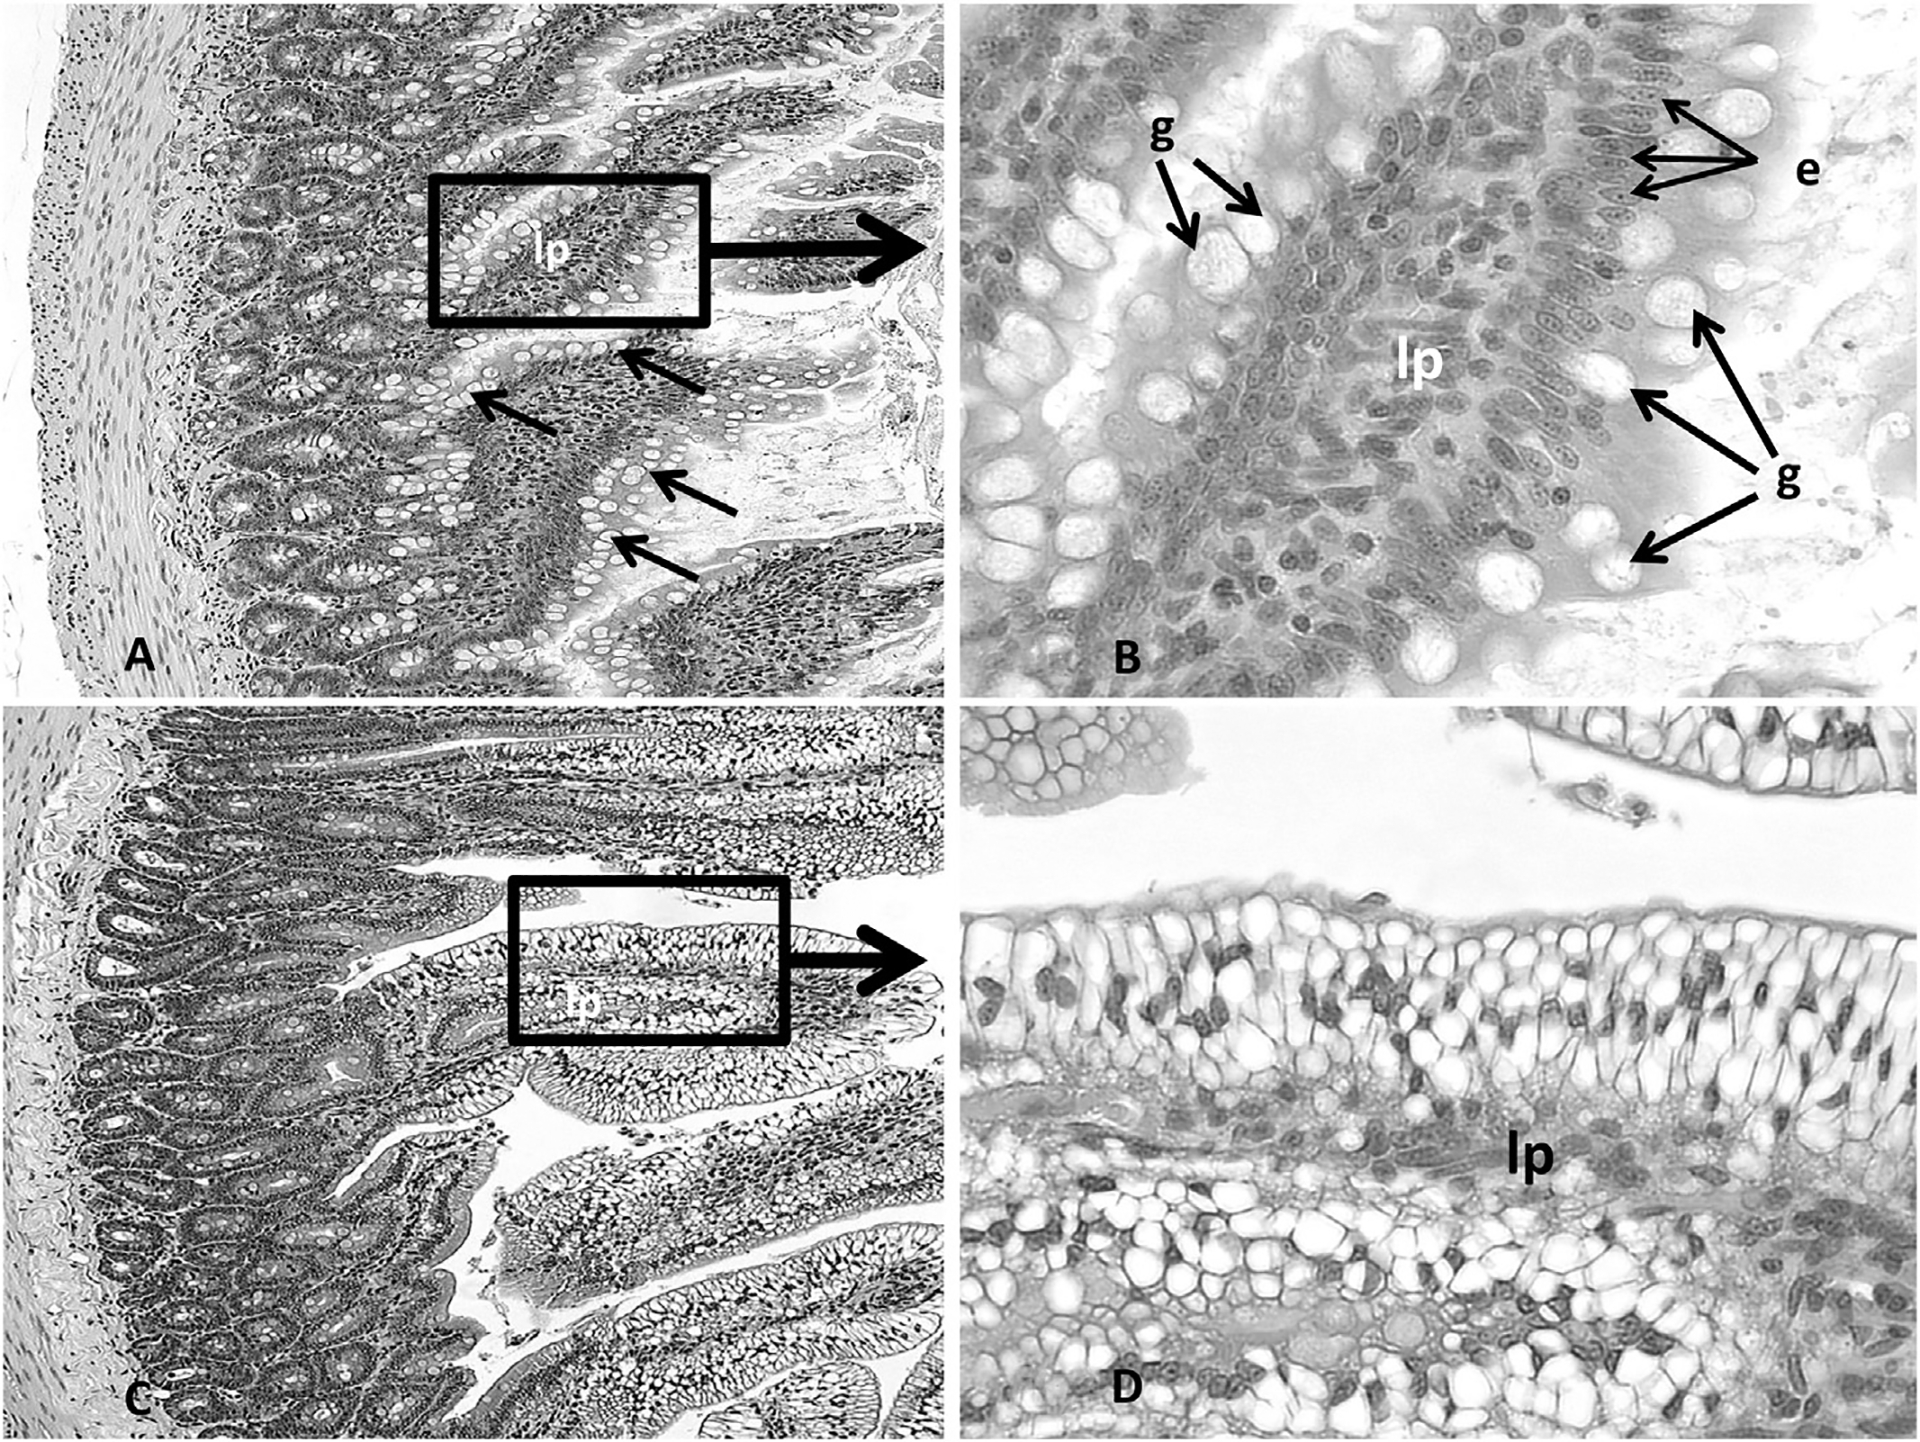

Histopathological analysis of organ sections from animals treated with 30 mg/kg bw or less revealed no adverse histopathological effects in any of the organs selected for analysis (thymus, spleen, stomach, liver, kidneys, adrenals, ovaries). At the treatment dose of 100 mg/kg bw, however, the kidneys uniquely showed evidence of change; minor renal tubule regeneration was the only microscopic observation. Regeneration was characterized by a flattened epithelium, tubule epithelial cell basophilia and nuclear crowding (Fig. 2A–F). Dose related effects were not observed in any other organs examined from the 100 mg/kg dose group. In contrast, extensive DGA exposure related damage occurred in multiple organs from animals in the 300 mg/kg bw. The severity of the response between the 300 mg/kg bw DGA dose group and the other DGA dose groups was dramatic. Renal failure occurred in this group at treatment Day 5, necessitating their removal from the study. As shown in Fig. 2G and H, marked effects were observed on the renal cortical proximal convoluted tubules. These effects included renal tubule vacuolar degeneration and necrosis, with evidence of renal regeneration and mineralization. Additional severe treatment related effects were observed in other organs examined and included microvesicular centrilobular vacuolization in the liver (Fig. 3A–D), necrosis and decreased numbers of cortical lymphocytes in the thymus (Fig. 4A and B), depletion of white pulp lymphocytes in the spleen (Fig. 5A and B), vacuolization of the lining epithelium in the stomach (Fig. 6A–D) and small intestines (Fig. 7A–D) and a decrease in the number of hematopoietic cells with a concomitant increase in the prominence of reticular stroma in the sternal bone marrow (Fig. 8A–D).

Representative photomicrographs (Fig. 7A, 200×; Fig. 7B, 400×) of the intestine from the control animals and animals exposed to DGA at concentrations up to and including 100 mg/kg body weight. Note the intact lamina propria (lp), goblet cells (g) and columnar epithelium (e) lining the villi. The animals exposed to 300 mg/kg bw DGA showed a marked vacuolization of the epithelial cells lining the intestinal villi (Fig. 7C, 200× and 7D, 400×).